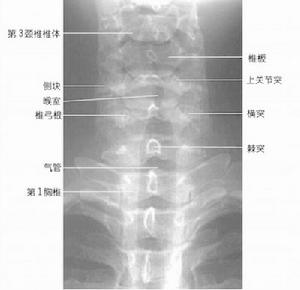

①主訴頭、頸、肩疼痛等異常感覺,並伴有相應的壓痛點。②X線片上頸椎顯示曲度改變或椎間關節不穩等表現。③應除外頸部其他疾患(落枕、肩周炎、風濕性肌纖維組織炎、神經衰弱及其他非椎間盤退行性變所致的肩頸部疼痛)。

①臨床上出現頸脊強損害的表現。②X線片上顯示椎體後緣骨質增生、椎管狹窄。影象學證實存在脊髓壓迫。③除外肌萎縮性脊膀例索硬化症、脊髓腫瘤、脊髓損傷、繼發性粘連性蛛網膜炎、多發性末梢神經炎。